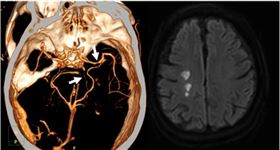

染新冠不僅侵犯呼吸道 恐引發腦中風

臺中榮民總醫院除了防疫工作,也致力研究,從治療新冠肺...